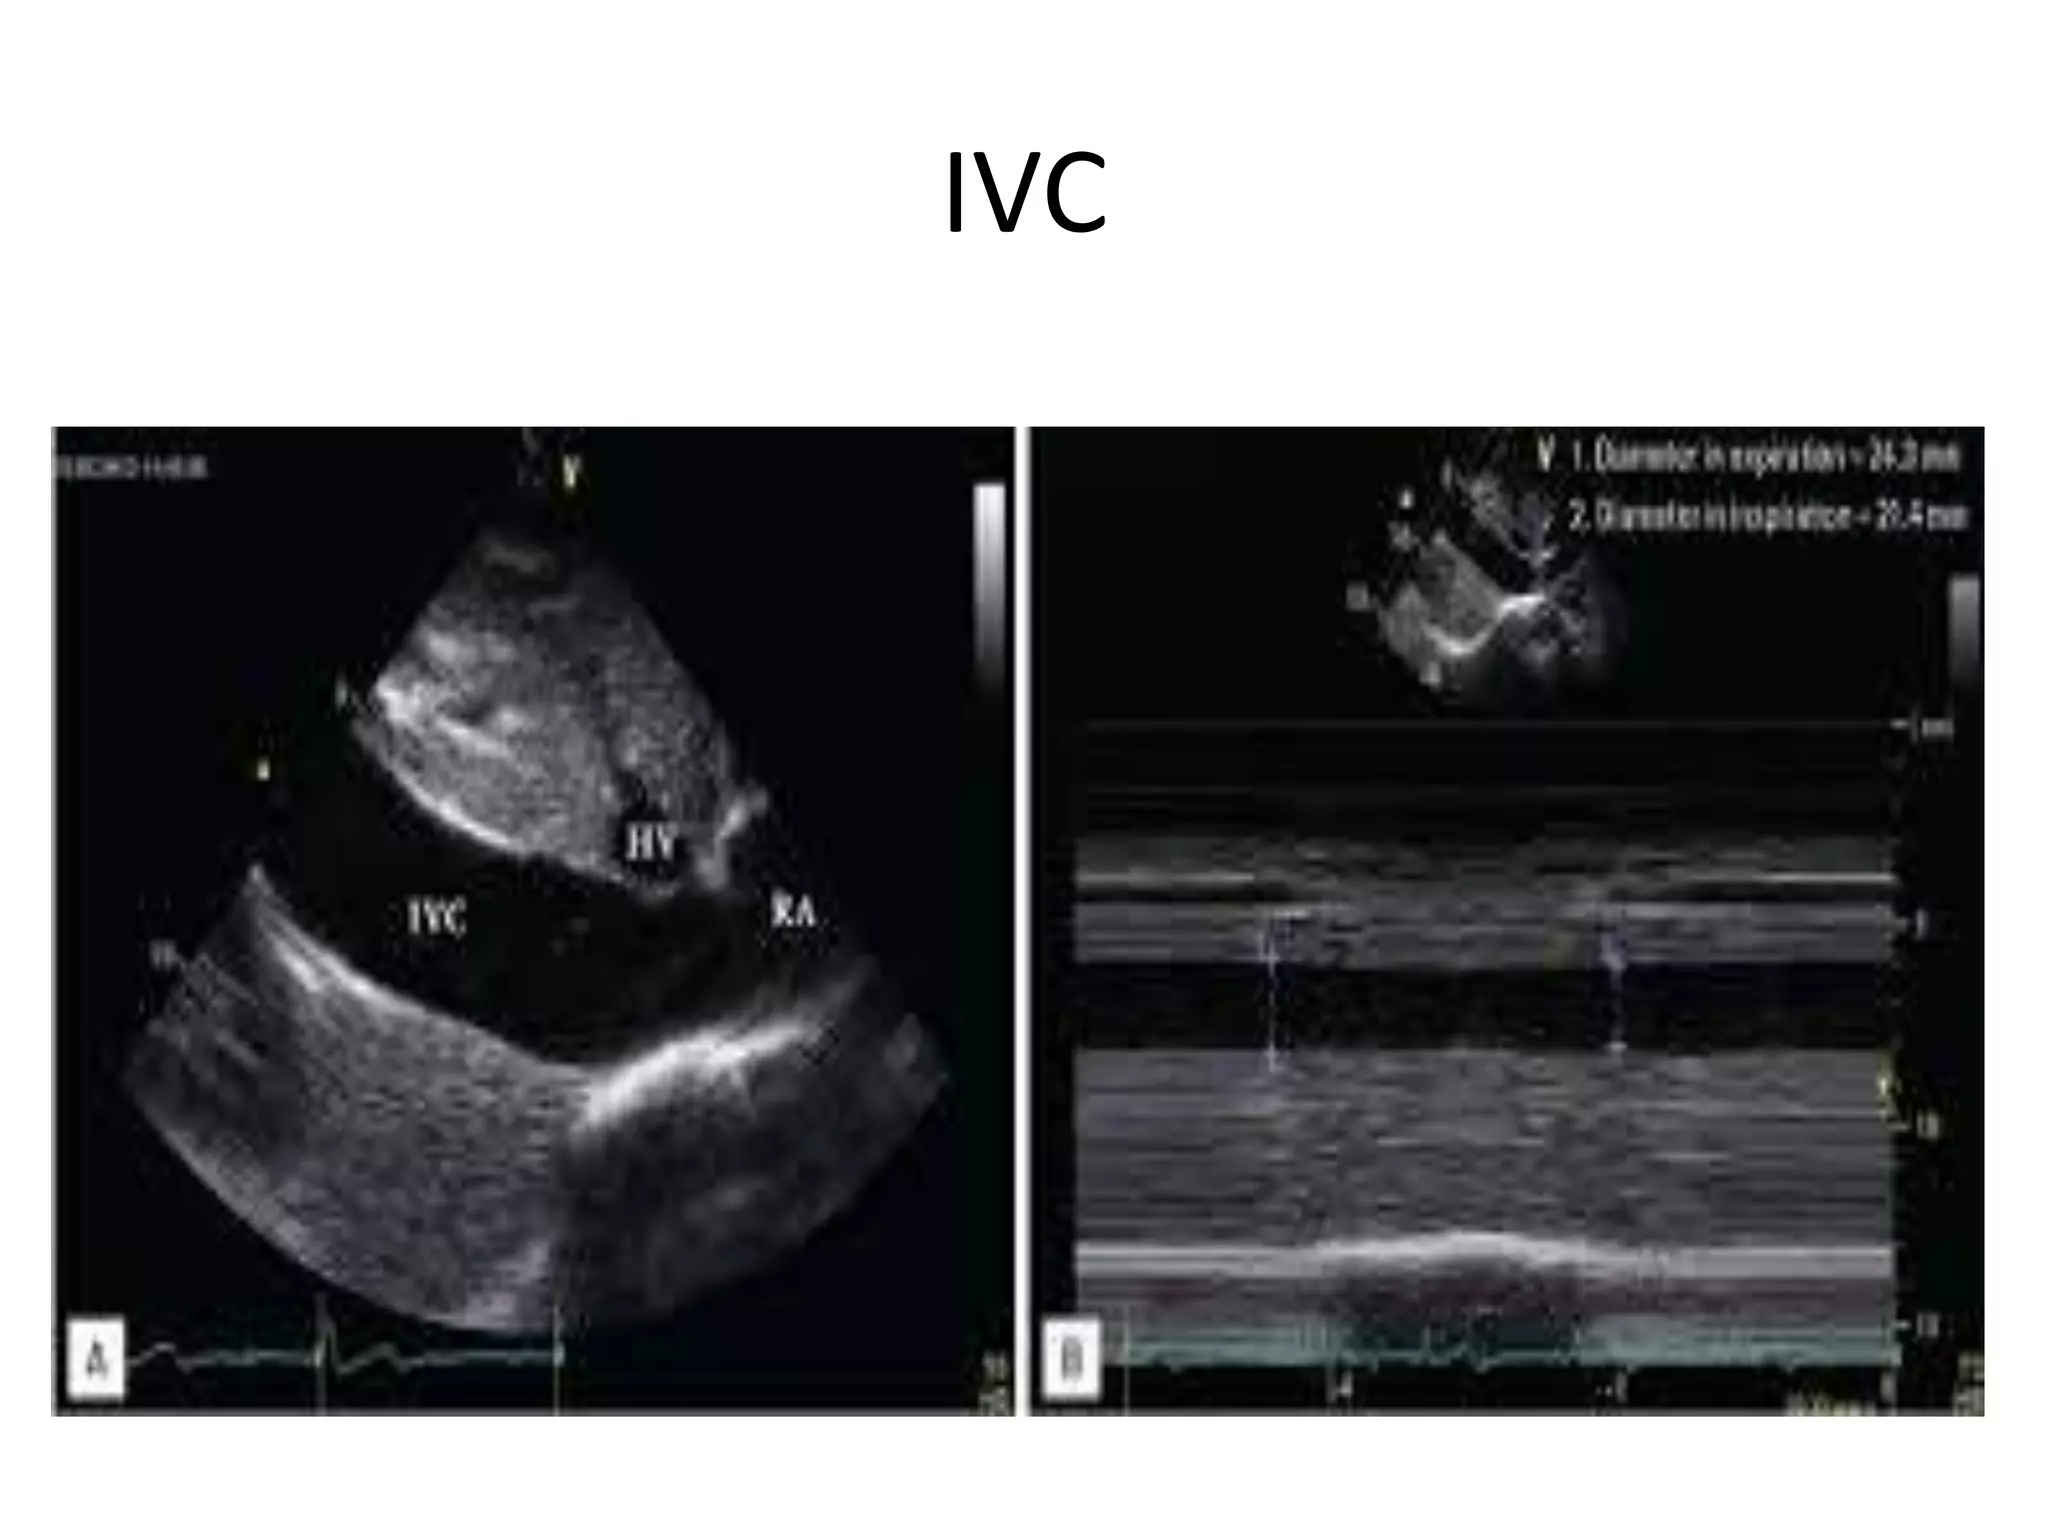

IVC